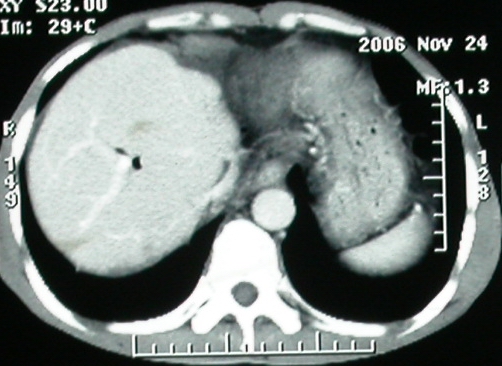

平扫

4、右肝后上段占位(考虑肝胆管结石伴肝组织萎缩?)

ct表现:1,胰腺钩突后方肿块,不均强化,中心密度低,钩突及门静脉前移。2:肝右后叶不均强化灶,突出肝表面,3:胆囊明显增大,肝内胆管及肝总管内积气。4:腹腔内少量积液。

考虑:1:胆囊炎,胆管炎。2:肝癌合并腹腔内转移灶,腹水。

胰头后方肿块,周边强化,胰头受压推移,肝脏右后叶异常强化灶,首先考虑肝癌后腹膜淋巴结转移;2、肝内胆管积气。

补充一点重要资料:今日查afp大于正常值10倍以上。因此,本病例最大可能应该是肝癌。

手术结果:

肝脏尾状叶肝癌(沿肝十二指肠韧带向下韧带内生长,门腔间隙外压增大),大结节性肝硬化,胆囊积脓,胆道感染。术中见肝外胆道2cm直径,肿瘤向前压迫胆管至扁平状态。